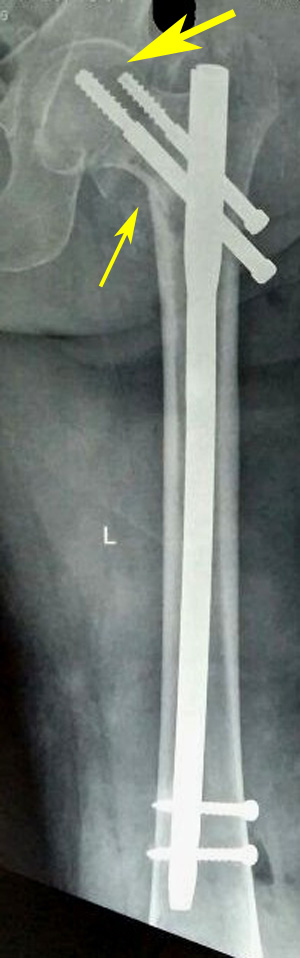

Figure 1a Varus reduction as demonstrated by medial overlap of fragments (thin arrow). Also note lateralization of entry point (thick arrow).

Figure 1b Manipulation with Steinmann pin to correct neck shaft angle as demonstrated by medial continuity and correction of overlap (arrow).